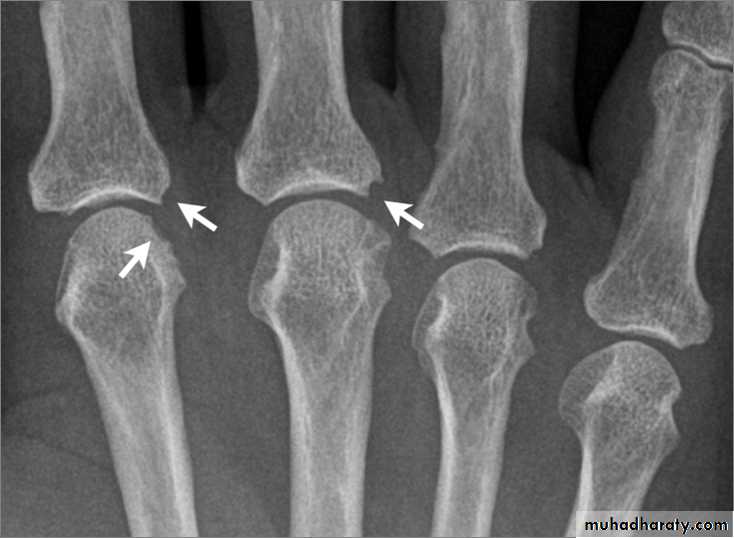

Ревматоидный артрит стопы: рентгеновские снимки и стадии заболевания